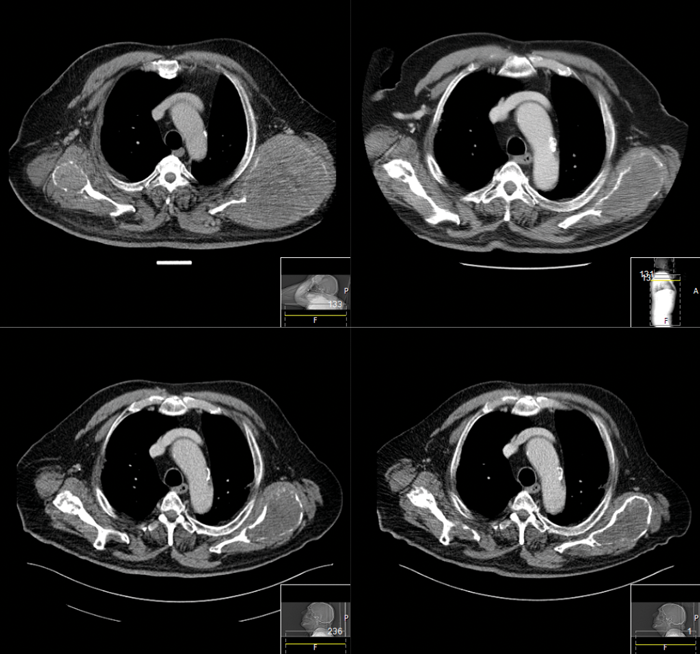

Surgical challenges in advanced or recurrent thyroid malignancy

The management of thyroid malignancy and extent of surgery is controversial, especially considering the limitations of preoperative diagnosis. Neil Tolley provides guidance and reminds us of our responsibility not to over-treat. In the UK, 16% of thyroidectomies are performed for...